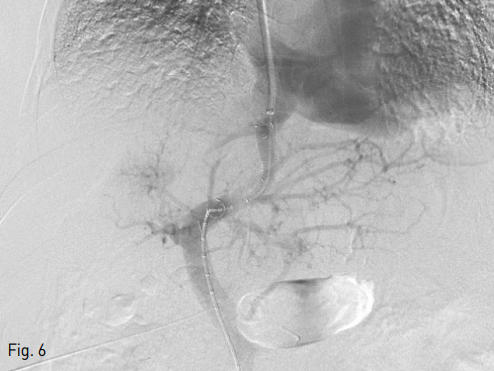

Fig 6

Final portography showed successfully established shunt tract via left portal vein.

시술을 위해, 우선 초음파 유도하에 우측 내경정맥을 천자한 후, Ring transjugular intrahepatic access set (Cook, Bloomington, IN, USA)내의9-Fr sheath (Cook, Bloomington, IN, USA )를 삽입하였고, 우측 총대퇴동맥을 천자하여 5-Fr vascular sheath (Terumo, Tokyo, Japan)를 삽입하였다. 5-Fr RH catheter (Cook, Bloomington, IN, USA) 를 이용하여 상장간동맥을 선택하여 간접문맥 조영술을 시행하였을 때, CT 소견과 마찬가지로, 우측 간문맥의 크기가 매우 작아져 있어 우간정맥에서 간문맥을 천자하기가 어려워 보였다 (Fig. 2). 이에 따라서, 좌간정맥으로부터 좌측간문맥으로의 단락을 만들기로 계획하였다. 우측 내경정맥의 9-Fr sheath를 통해, 5-Fr multipurpose catheter(Cook, Bloomington, IN, USA) 및 0.035-inch guide wire를 삽입하여 좌간정맥의 선택을 시도하였으나 실패하였다. 이에, 경피경간으로 좌측 간문맥과 좌간정맥을 연이어 천자하는 방법을 시도하기로 하였다. 먼저, 시술전 시행한 CT영상으로 3차원 재구성 영상 기법을 이용하여, 좌측 간문맥을 초음파 유도하에 천자할 때와 유사한 사위축상면 영상을 재현했다 (Fig. 3). 이 영상을 참고로 하여 초음파 유도하에 21 Gauge Chiba needle로 좌측 간문맥의 3번 구역지를 천자하였다. 간문맥이 천자된 것을 소량의 조영제로 확인후, 바늘을 조금 더 전진시켜 좌간정맥을 천자하는데 성공하였다. 이후, 0.035-inch guide wire를 우측무명정맥까지 진입 시킨 후, 우측 내경정맥에 있는 9-Fr sheath를 통해 snare catheter를 삽입하여 이 guidewire를 잡아 9-Fr sheath 로 꺼내는데 성공하였다 (Fig. 4). 이 guidewire를 이용하여 5-Fr DAVIS catheter (Cook, Bloomington, IN, USA) 를 좌측 간문맥을 지나 상간정맥까지 위치시키는데 성공하였다 (Fig. 5). 이때 측정한 문맥체정맥 압력차는 49 mmHg였었다. 0.035-inch guide wire를 Amplatz Super Stiff Guidewire (Boston Scientific, Boston, MA, USA)로 바꾼 후 , 8mmX4cm Mustang balloon catheter (Boston Scientific, Boston, MA, USA)을 이용하여 tract을 확장한 후, 10mmX5cm self-expandable stent (niti-s vascular stent, Taewoong, Korea)를 삽입하였다. 그 후 측정한 문맥체정맥 압력차는 27 mmHg로 감소하였으며, 시술 후 시행한 문맥조영술 상 간내문정맥 단락을 통한 흐름이 유지됨을 확인하였다 (Fig. 6). 좌측 간문맥의 3번 구역지를 천자했던 경로를 3mm × 3cm MReye Embolization Coil (Cook, Bloomington, IN, USA) 과 histoacryl과 lipiodol을 1:5로 혼합한emulsion을 이용하여 색전하고 시술을 종료하였다.